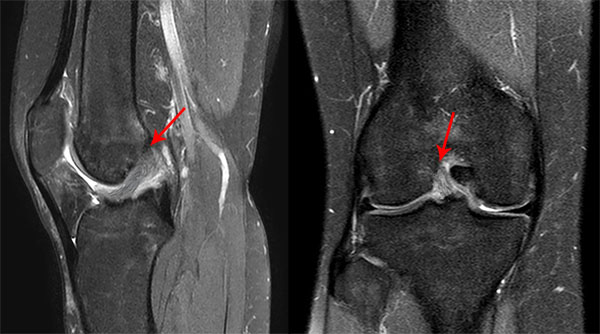

Paciente femenino de 44 años, esquiadora recreativa, que consulta a nuestra institución el 22 de julio del año 2018, por un cuadro de dolor, limitación funcional e inestabilidad anterior de rodilla derecha posterior a un traumatismo deportivo (ski en nieve) de 1 semana de evolución. El examen físico reveló una prueba de Lachman positiva (++), pivot shift positivo (+), derrame articular con choque rotuliano positivo (+++) y test de McMurray (+) para menisco interno. El diagnóstico de lesión completa tipo I (avulsión femoral) del LCA según la clasificación de Sherman28 (fig. 1) y lesión vertical longitudinal periférica del cuerno posterior del menisco interno, se confirmó por resonancia magnética nuclear (RMN) de rodilla (fig. 2).

Figura 2: A) Imagen que muestra un corte sagital de Resonancia Magnética Nuclear (RMN) de rodilla donde se observa la avulsión proximal y el remanente del LCA. Flecha Roja (FR): Avulsión Femoral del LCA. Flecha Amarilla (FA): Remanente Completo del LCA. B) Imagen que muestra un corte coronal de Resonancia Magnética Nuclear (RMN) de rodilla derecha donde se observa la avulsión del LCA en su inserción proximal femoral y la lesión del Menisco interno. FR: Avulsión femoral del LCA. FA: Lesión del menisco interno. C) Imagen que muestra un corte sagital de Resonancia Magnética Nuclear (RMN) de rodilla derecha donde se observa la lesión del cuerno posterior del Menisco interno. FR: Lesión del cuerno Post. del Menisco Int.